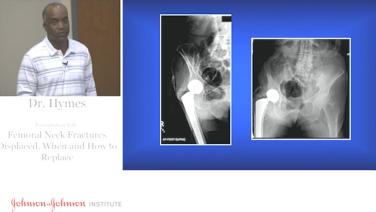

Displaced Femoral Neck Fractures - When & How to Replace with Robert Hymes, MD